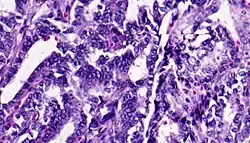

![]() | Renal cell carcinoma | Micrograph of clear cell renal cell carcinoma showing cells with clear cytoplasm, typically arranged in nests and nuclear atypia. | Category: Histopathology of renal cell carcinoma | Renal cell carcinoma |